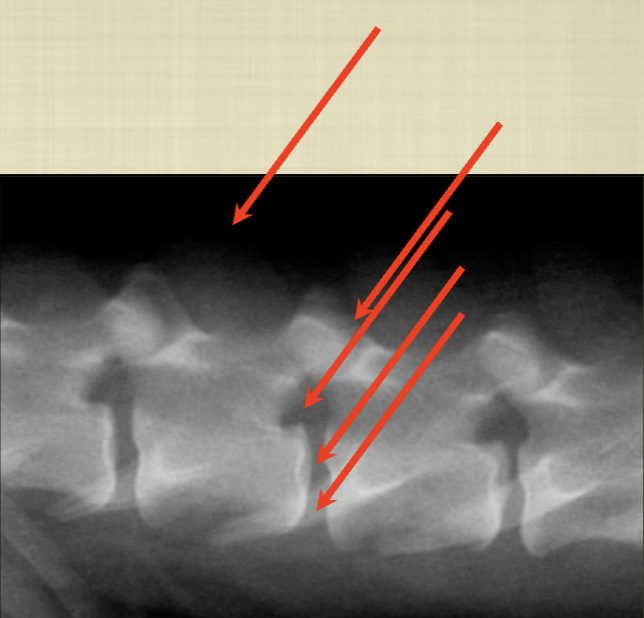

What are the abnormalities shown in this radiograph?

A

-articular joint space is closer together

-vertebrae are closer together (smaller disc space)

-intervertebral foramen is smaller